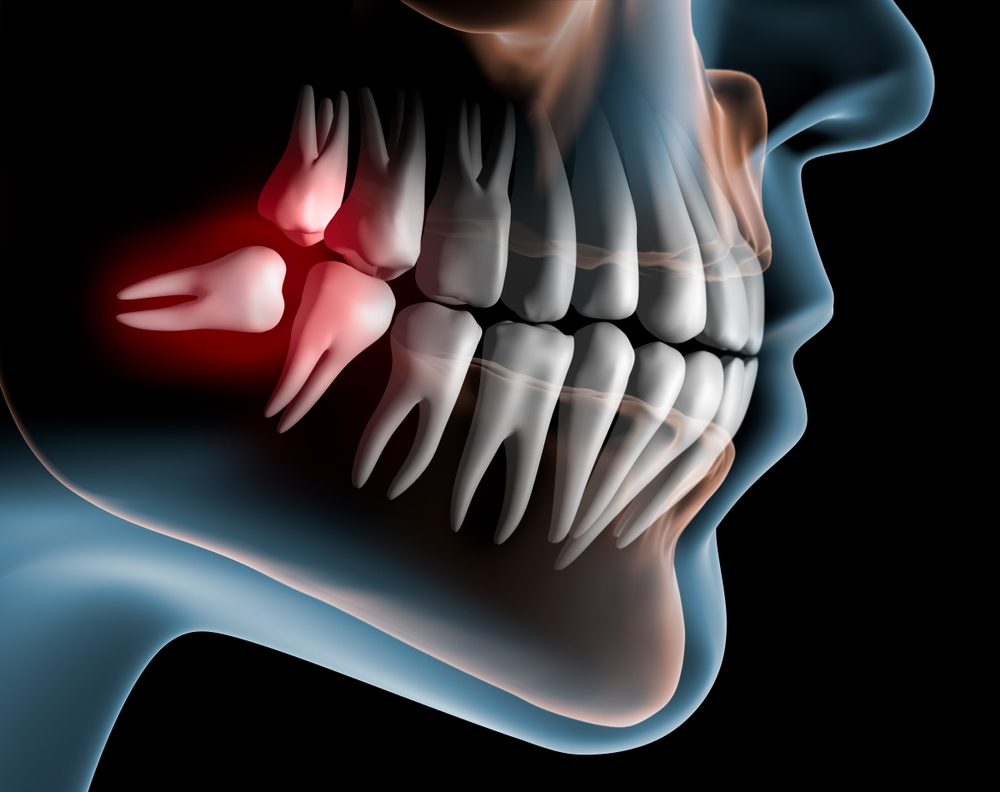

The extractions of impacted teeth are a completely different need but also can cause the same issue. In this situation, the teeth need to be removed because 1) the lack of space in the bone means the teeth cannot erupt or 2) the tooth is growing in the wrong direction or position. In this situation, the stress placed on the jaw joint can cause the disc to be displaced and in addition, put a strain on the muscles around the jaw joint.